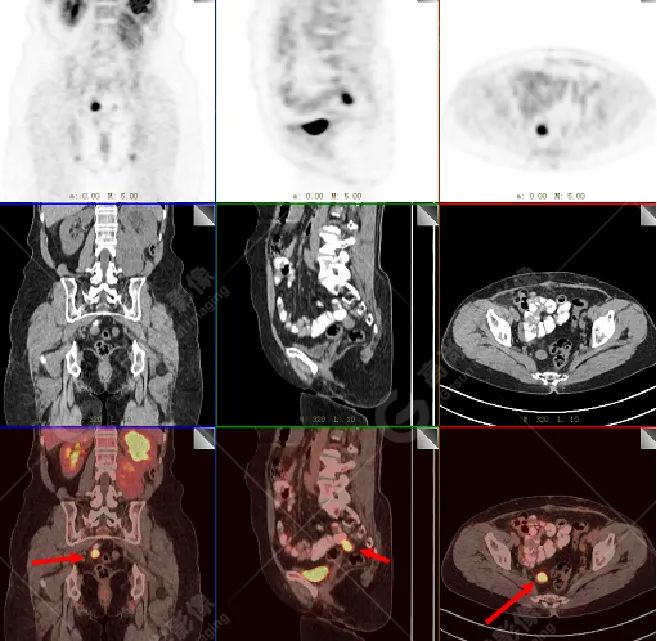

影像所见:左腹膜后间隙(原术区)见一长椭圆形软组织密度肿块影,范围约 8.0 cm×6.6 cm×15.8 cm,CT 值 30 Hu,FDG 高摄取,SUVmax5.0,考虑肿瘤复发,侵犯相邻左侧输尿管、腰大肌、后腹壁。

盆腔内(直肠右旁)见一转移性淋巴结,FDG 高摄取,SUVmax7.7。

增强扫描肿瘤不均性中度强化,动、静脉期 CT 值:41 Hu、72 Hu(平扫 CT 值 30 Hu)。